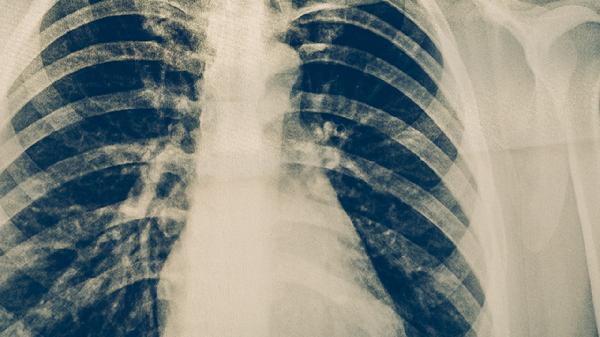

肺结核可通过化学药物治疗、手术治疗、营养支持治疗、隔离防护措施、中医辅助治疗等方式治疗。肺结核通常由结核分枝杆菌感染引起,主要表现为咳嗽、咯血、午后低热等症状。

手术治疗适用于药物治疗无效的慢性纤维空洞型肺结核,或合并大咯血、支气管胸膜瘘等并发症的情况。常见术式包括肺叶切除术、全肺切除术等。术前需评估肺功能储备,术后仍需继续抗结核治疗以防止复发。手术风险包括术后感染、呼吸功能代偿不全等。

肺结核患者应保证每日8小时睡眠,避免过度劳累。居室温度维持在20-24摄氏度,湿度50%-60%为宜。戒烟限酒,减少呼吸道刺激。康复期可进行散步、太极拳等温和运动,运动强度以不引起明显气促为度。定期复查胸部影像学和痰检,全程完成药物治疗是治愈的关键。出现药物不良反应或症状加重时须及时复诊调整方案。